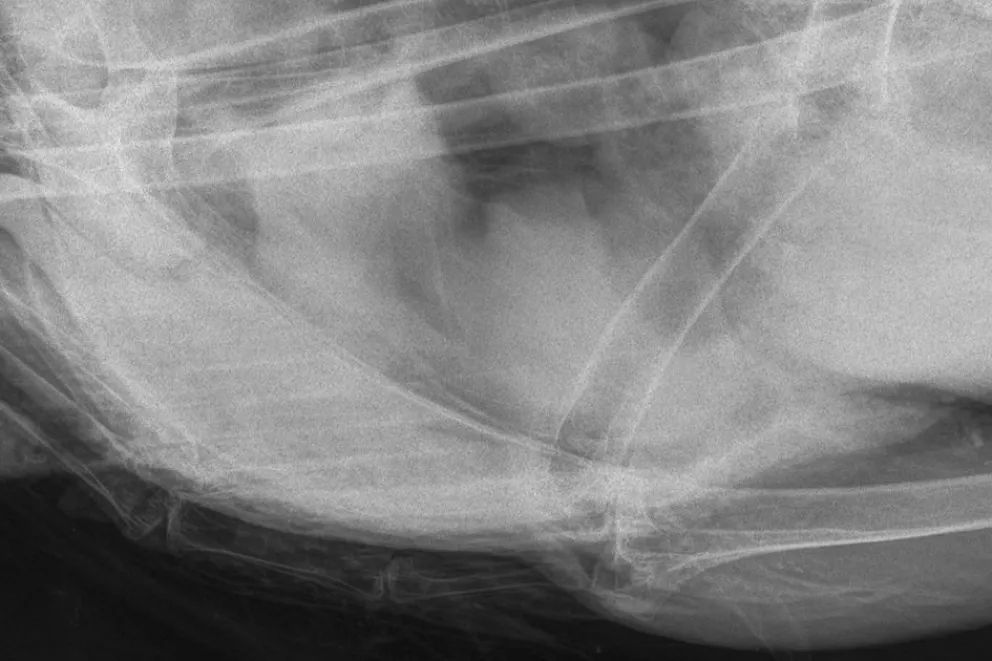

Se procedió a trasladarla hasta Chos Malal, donde se dio aviso al veterinario Gustavo González, quien se hizo presente acompañado por la veterinaria Magalí López, ambos profesionales de dicha localidad. Durante la revisión, se aplicaron anticoagulantes y se recomendó la realización de una radiografía, ya que el ejemplar presentaba un orificio y se buscaba descartar la presencia de plomo.

El estudio no evidenció presencia de plomo, aunque sí se observó una pequeña hemorragia interna. Las causas de la herida no pudieron determinarse con certeza; se presume que podría haberse tratado de un impacto de bala que no llegó a ingresar.

“No tiene nada quebrado, los veterinarios lograron parar la hemorragia y le brindaron toda la atención necesaria”, afirmó Lagos.